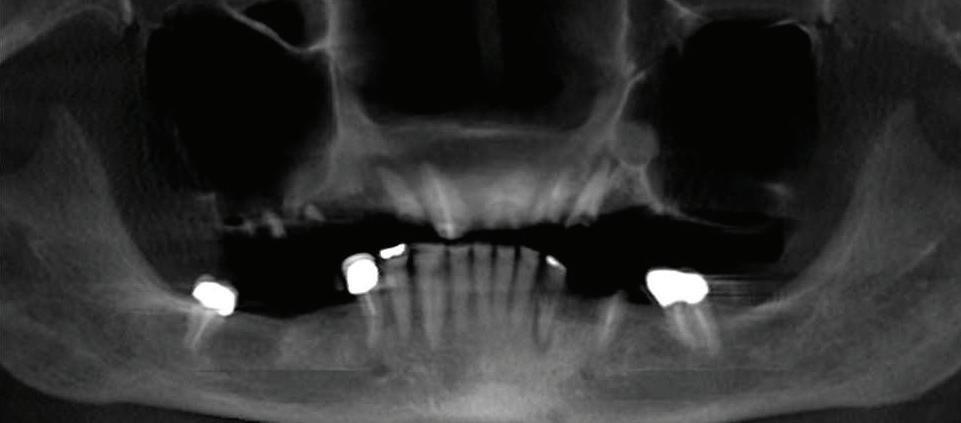

Submitted By Sivakumar Sreenivasan, DMD, MDS Dental Implant Center of Rockville

Tooth loss is extremely common among adults, especially as we age. Rather than living with the discomfort and hassles of dentures, many people are opting for what is called “all-onfour” dental implant restoration.

An implant is a small titanium

screw that fits inside your jawbone and replaces the root-part of a missing tooth. Minor surgery is required to insert the implants. Once the implant is in place, a crown is attached to give you a highly realistic-looking and functional prosthetic tooth.

You do not need a dental implant for each and every one of your missing teeth. All you need is four precisely placed implants on the top of your mouth, and four on the bottom, to restore your full smile. That’s the beauty of the all-on-four. And because the implant is made of titanium, it has the unique ability to fuse to living bone and function as part of it. So eventually, the dental implant becomes part of the jawbone and serves as a strong, longlasting foundation for your new teeth.

Besides ensuring that your implants are permanently fixed in place, this bone fusion has another important benefit: it prevents future bone loss in the jaw. This helps to maintain a more youthful facial structure – and better